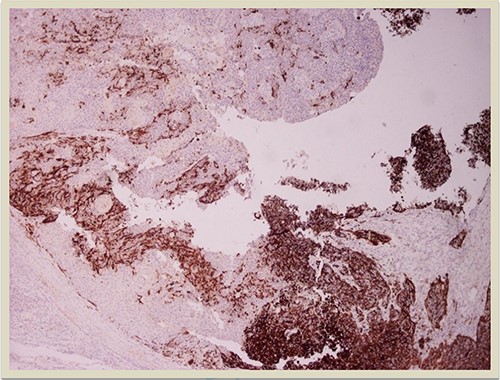

A 69-year-old man was admitted to our hospital with a nodular skin tumor of the back (Fig. 1). The patient had no ongologic history. We performed excisional biopsy that revealed collision tumor. The collision tumor consisted of mixed melanosquamous tumor (dermal squamomelanocytic tumor) together with BCC (Fig. 2). The BCC was superficial spreading. The mixed element contained squamous cell carcinoma of well/moderately differentiated and a neoplasm with melanotic characteristics, which due to cell atypia, presence of mitoses and high index of cell proliferation (Ki67: 80%) was described as melanoma (Fig. 3). Diagnosis of the melanotic and the squamous element was confirmed with immunohistochemistry (Figs 4 and 5).

p63 × 10: p63 immunostain confirms the presence of squamous cell carcinoma component (×10 magnification).

Histologically the collision tumor involves two different and distinct entities. There is no interaction between the tumor cells of the two different neoplasms. The paradox in our case is that the melanotic cells were admixed with squamous cells. The histopathologic findings of the combined tumor were confirmed with immunohistochemistry. Squamous element was confirmed from the positivity of the stains: AE1/AE3, EMA and CK5. Melanotic element was also confirmed with the following stains: Vimentin, S-100, MART-1(Melan-A) and HMB45. Histologic findings and immunohistochemical stains confirmed the combined melanosquamous neoplasm in the collision tumor, which does not seem to involve epidermis. Reviewing the literature, we did not find any other case of a combined neoplasm in a collision formation.